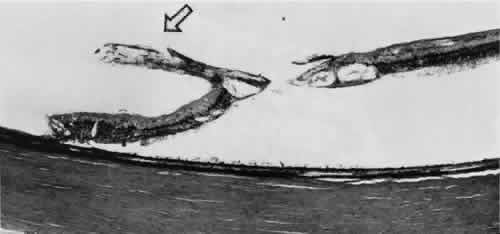

Fig. 12. Enclosed ora bay in a 35-year-old man. Anteriorly, two broad dentate processes

converge and join to enclose a bay (island of pars plana). Posteriorly

there is a focus of retinal thinning (peripheral retinal excavation; arrow). (× 12.) Fig. 12. Enclosed ora bay in a 35-year-old man. Anteriorly, two broad dentate processes

converge and join to enclose a bay (island of pars plana). Posteriorly

there is a focus of retinal thinning (peripheral retinal excavation; arrow). (× 12.)

PERIPHERAL RETINAL EXCAVATION Peripheral retinal excavation appears as a rather small oval depression

in the retina. Usually this lesion is aligned meridionally with a meridional

fold or complex and located 1 to 7.2 mm posterior to the ora serrata (Fig. 13; see Figs. 6 and 12). The focal depression may be surrounded by margins that appear to be

elevated; however, microscopic examination reveals that the depression

corresponds to afocal loss of the inner retinal layers and that the surrounding

tissue is normal (Fig. 14).  Fig. 13. Meridional complexes with peripheral retinal excavation. Two complexes

can be seen anteriorly; both contain meridional folds (the fold of complex

on the right is discontinuous). Peripheral retinal excavation (arrow) is aligned with the complex on the left (× 12.) Fig. 13. Meridional complexes with peripheral retinal excavation. Two complexes

can be seen anteriorly; both contain meridional folds (the fold of complex

on the right is discontinuous). Peripheral retinal excavation (arrow) is aligned with the complex on the left (× 12.)